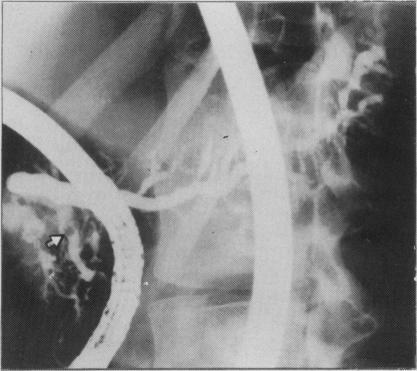

US-guided percutaneous pancreatography: an essential tool for imaging pancreatitis.

Radiographics. 1992 Jan;12(1):79-90. doi: 10.1148/radiographics.12.1.1734484.